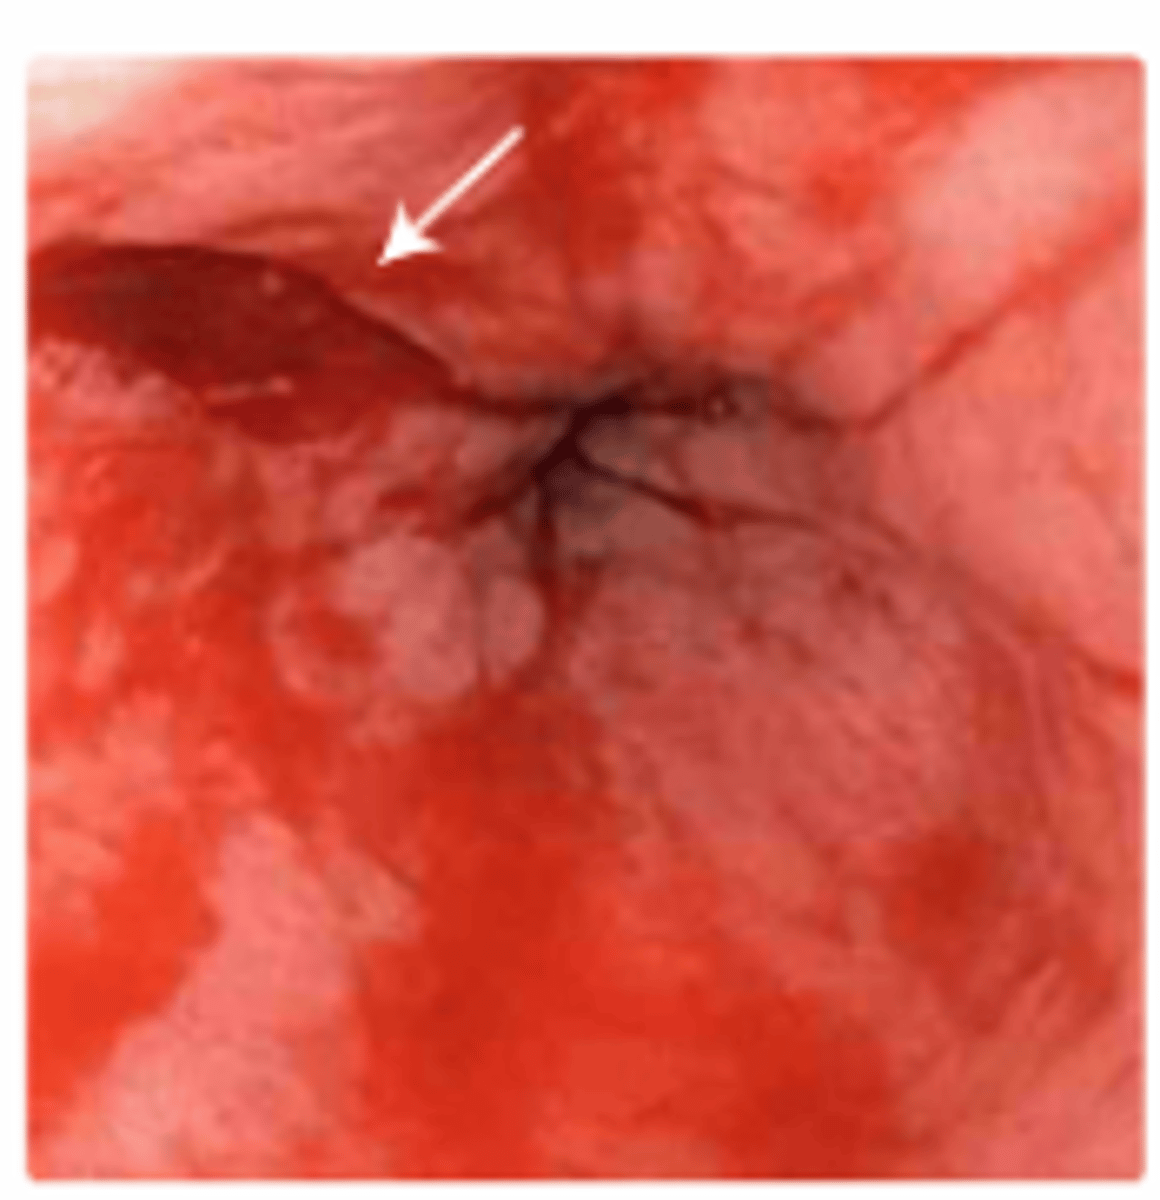

Mallory-Weiss Syndrome

RF: Alcohol Use, Hiatal Hernia, Bulimia

Dx: Suspected in patients with upper GI bleed and history of vomiting or retching

- Confirmed by upper endoscopy

PE: Acute-onset GI Bleeding (Hematemesis)

-> History of non-bloody emesis, retching, coughing prior to hematemesis

Management:

- Supportive

- Endoscopic therapy (active bleeding)

- Acid suppression (No active bleeding)